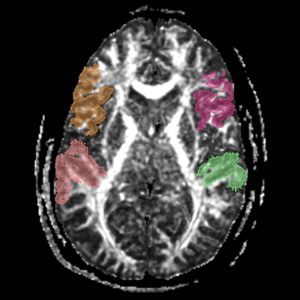

Arcuate Fasciculus

These labelmaps ('caseD00XXX-FS-arcuate-final.nhdr') were created using automatic gray matter parcellation in Freesurfer and coregistered in Slicer to corresponding DTI dataset. The labelmaps were dilated in Slicer to increase coverage of gray matter.

Figure 12. Gray matter ROI's for Arcuate Fasciculus tractography

Figure 13. Gray matter ROIs (right side) in 3D

The color coding of the resulting ROIs is as follows:

ROI 1: Superior Temporal Gyrus - Left(5) - Right(6)

ROI 2:Inferior Frontal Gyrus- Left(13) - Right (14)